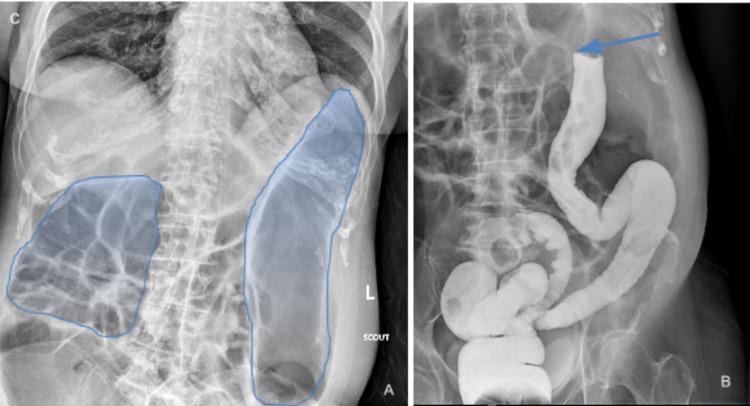

胰腺腺癌是仅次于结肠癌的第二常见胃肠道癌症。胰腺腺癌的检测存在延迟,因为许多人在其转移至身体不同部位之前都没有症状。我们报告一例78岁女性因胰腺癌导致大肠梗阻的病例,该病例在剖腹探查术中被发现。尽管胰腺癌的发病率有所上升,但尚未制定用于早期检测和治愈的筛查指南。临床医生应将胰腺癌纳入高危人群的鉴别诊断中。

A Unique Case of Exploratory Laparotomy in the Setting of Large Bowel Obstruction Led to the Detection of Pancreatic Carcinoma.一例因大肠梗阻行剖腹探查术而发现胰腺癌的独特病例。